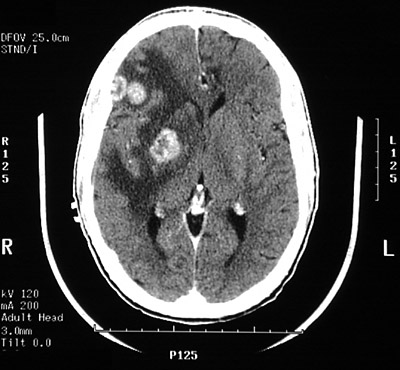

This cerebral CT scan in axial view demonstrates several ring enhancing lesions with surrounding edema that are typical for toxoplasmosis.